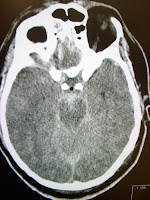

1. A 60-year-old woman with a history of hypertension presents to your ED lethargic

2. A 26-year-old man presents to your ED after being thrown 15-feet off of his motorcycle

3. A 42-year-old woman who complains of the worst headache of her life and neck pain

4. A 77-year-old man who tripped over the curb and fell to the ground

1. Intracerebral bleed

2. Epidural bleed

3. Subarachnoid hemorrhage

4. Subdural hematoma